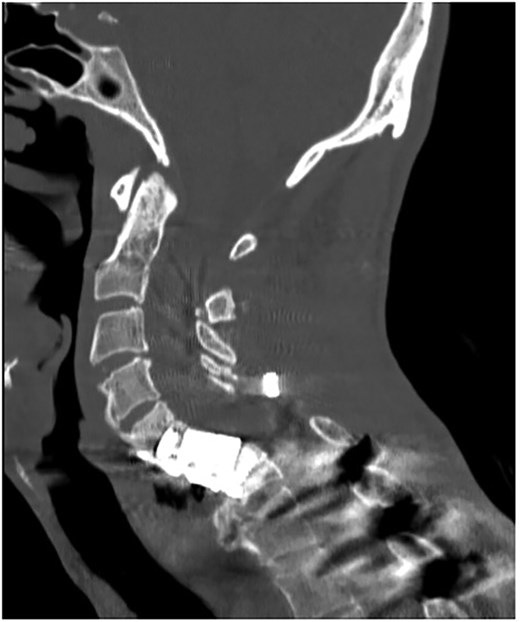

A 35-year-old male presented with a month-long history of dysphagia, severe headache, and posterior neck pain that radiated to the occiput. His medical history was significant for cervical surgeries, including an anterior cervical discectomy and fusion (ACDF) at C5/C6 one year and two months ago (Fig. 1). Shortly thereafter, the patient underwent revision surgery along with posterior plating from C5 to T1 due to osteomyelitis, worsening cervical deformity, and retropharyngeal abscess (Fig. 2). Initial workup included a noncontract computed tomography (CT), demonstrating increased gas density at C6 corpectomy site and post cricoid region (Fig. 3). A swallow study was obtained based on suspicion of a perforation and demonstrated extraluminal leakage of contrast posteriorly at the C6 level, consistent with initial CT (Fig. 4). Surgery included removal of the anterior and posterior hardware and esophageal repair. Although initially the esophageal injury was suspected to be related to the hardware, intraoperatively, it was found the instrumentation was not in communication with the esophagus. This confirmed the perforation was unrelated to direct injury from the cervical hardware construct, which was intact. The esophagus was repaired with a pectoralis flap. The postoperative course was uneventful, and the patient was discharged home after one week. The patient later died due to severe complications of substance abuse unrelated to the operation.

Initial sagittal CT without contrast after patient presented with symptoms of esophageal injury demonstrating increased gas density at the site of C6 corpectomy and post cricoid region.